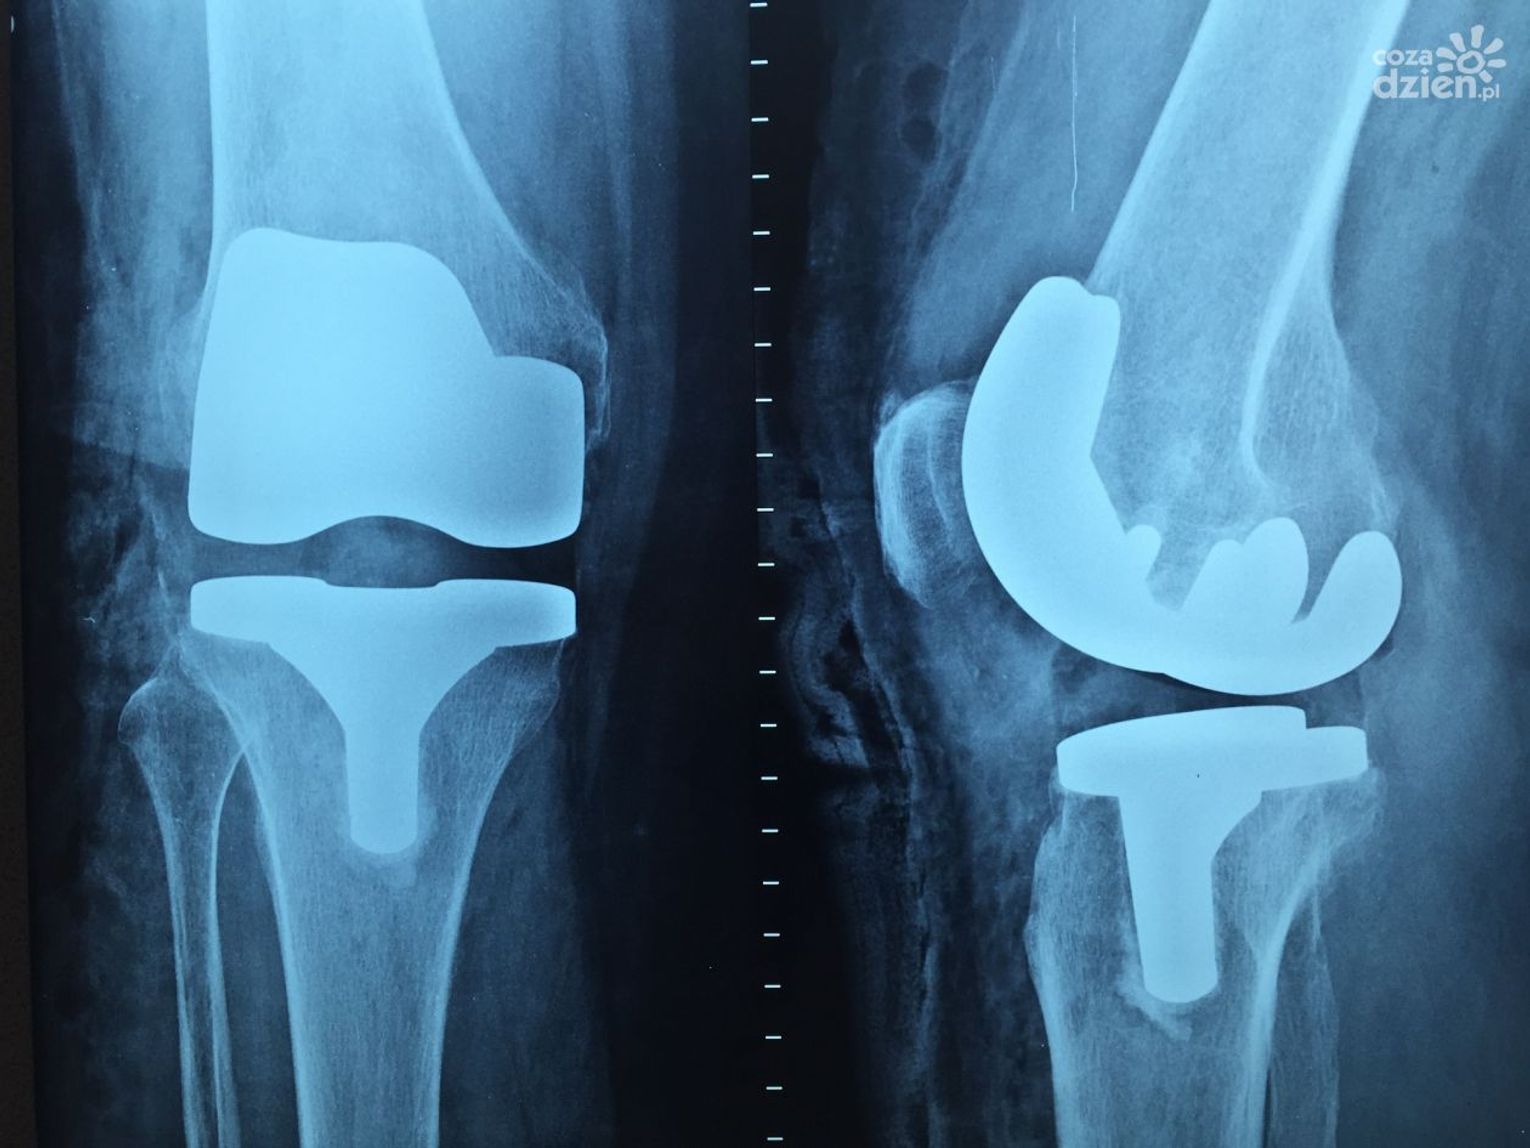

"Dominują tzw. urazy niskoenergetyczne, głównie to złamania nadgarstków, łokci, stawów skokowych, są to typowe urazy do których dochodzi w wyniku upadu na śliskiej nawierzchni" - informuje Anna Mazur Kałuża, rzecznik wojewódzkiego Szpitala Zespolonego w Kielcach.

Liczba pacjentów z urazami ciągle rośnie. Są one szczególnie niebezpieczne dla osób starszych, dlatego w taką pogodę nie powinny wychodzić z domów. W związku z tym, że temperatura pod wieczór wejdzie na lekki minus, sytuacja na chodnikach może się powtórzyć.